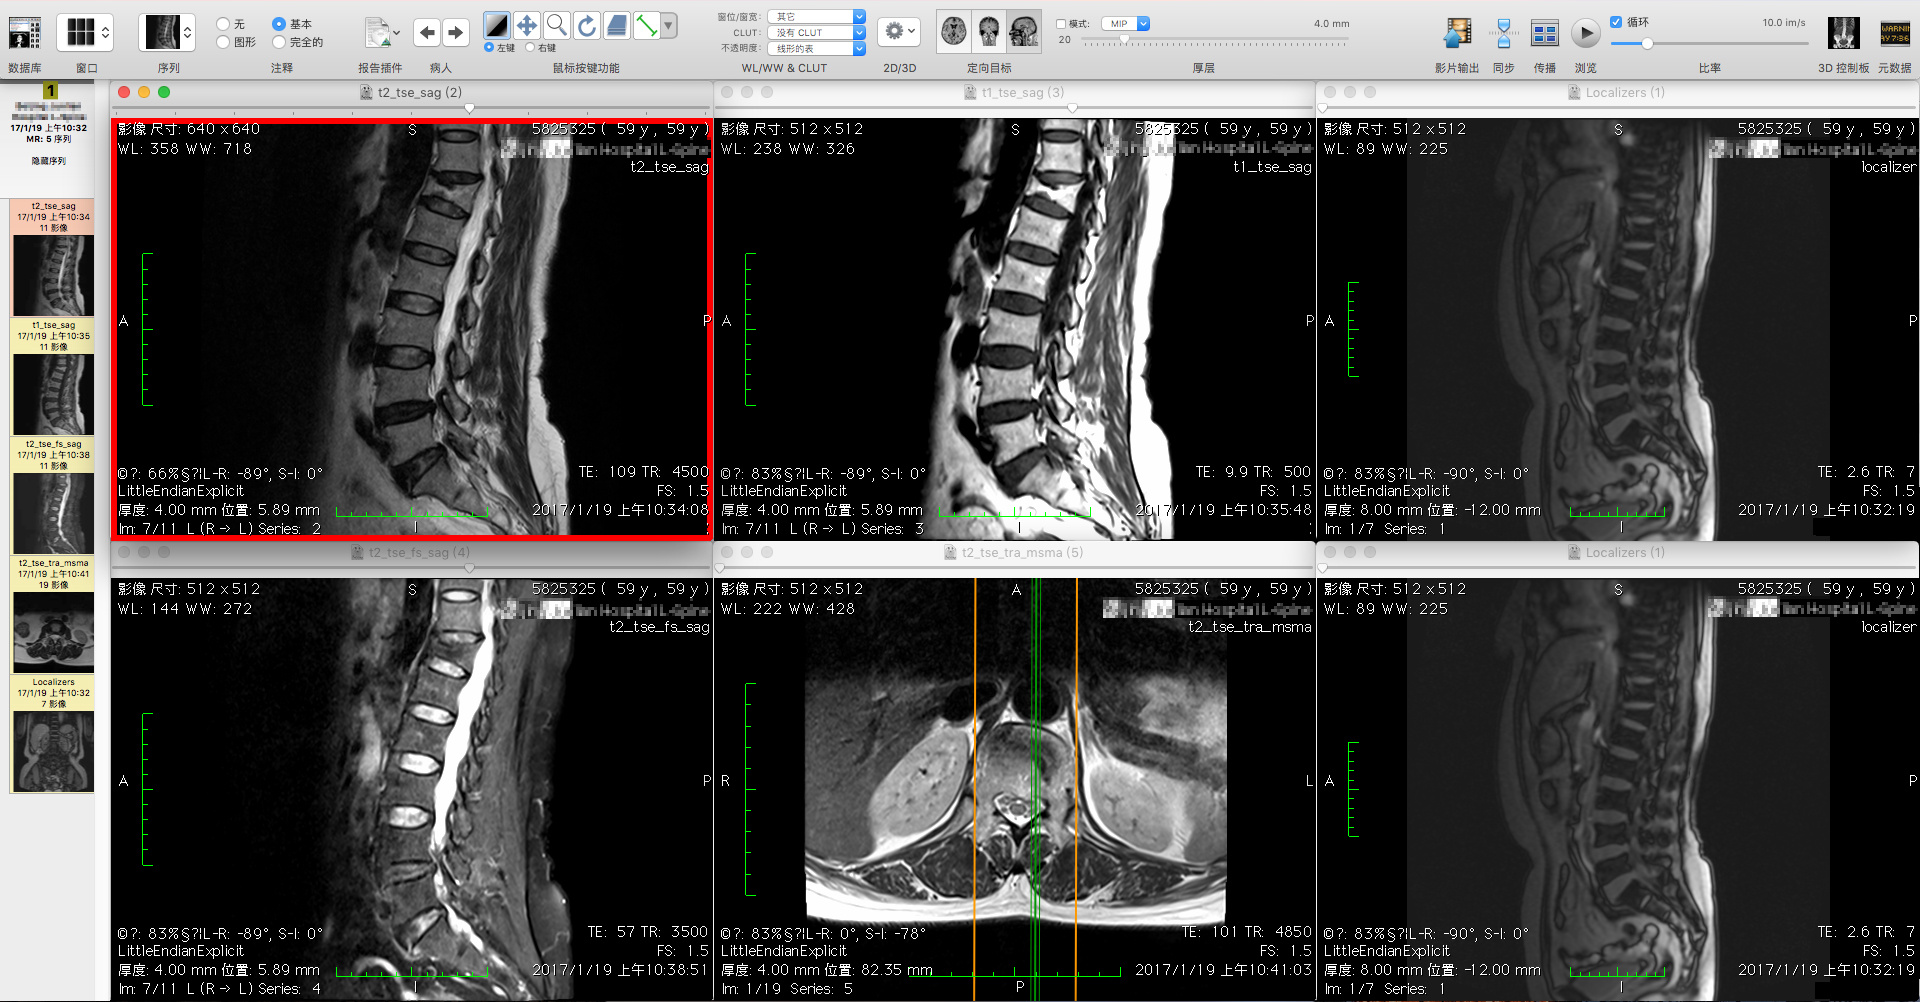

同心医联最初推出的产品为“易检查”,主要是为患者提供免费健康咨询和检查预约,通过其平台可以按照临床医生的要求,预约检查项目,完成检查后,将结果反馈给临床医生。而另一产品“快诊”则是医生端的产品,方便医生随时查看患者病例报告。在医院的影像科,同心医疗提供了云影像平台,可以替代医院PACS系统的功能,方便影像科医生在移动端阅片,撰写报告,完成影像后处理等工作。当遇到普通影像科医生不能判断的问题时,同心医联还可以对接专家,进行远程阅片。对于临床上有需求的用户,也同样可以通过同心医联对接临床专家,进行二次问诊。